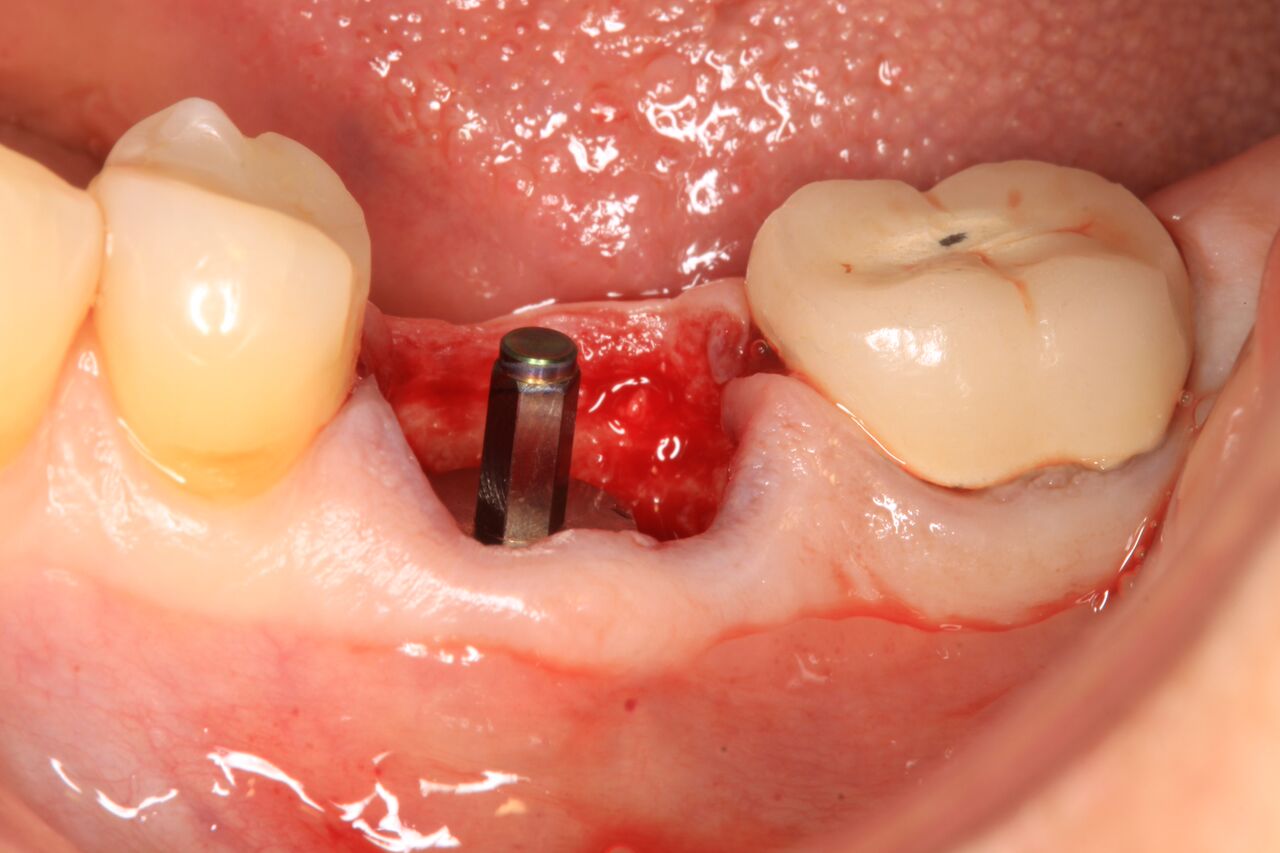

(2.) Immediate implant of No. 19 with temporization abutment.

Figure 2

A 63-year-old woman presented with severe pain on biting of tooth No. 19 (Figure 1). Clinically there was pain on percussion and significant periodontal probing along the mesial root. The patient was anesthetized with infiltration anesthesia and the crown was horizontally sectioned from the lingual of the tooth. The remaining tooth was sectioned so the roots could be extracted individually. The socket was fully debrided and an implant was placed (Figure 2), which was prosthetically correct and stabilized in excess of 45 Ncm. The bone was milled to allow for unimpeded placement of a temporization abutment. The initial crown was revised to be the temporary crown in infraocclusion. Cement was extruded extraorally (Figure 3) prior to seating of the temporary restoration. The socket was sealed with the temporary crown and there were no sutures or bone graft (Figure 4 and Figure 5).